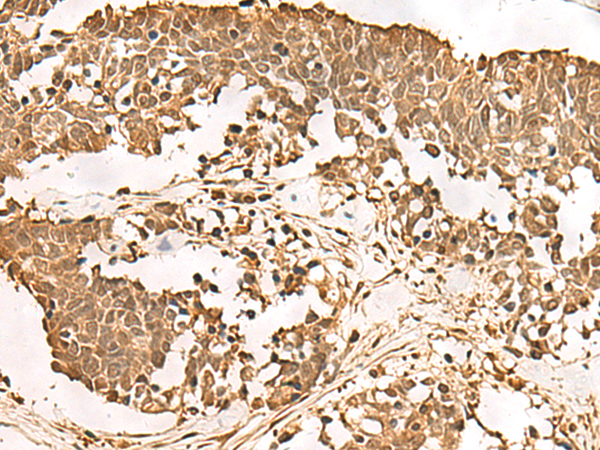

IHC positive control: |

Human ovarian cancer and Human thyroid cancer |

IHC Recommend dilution: |

40-200 |